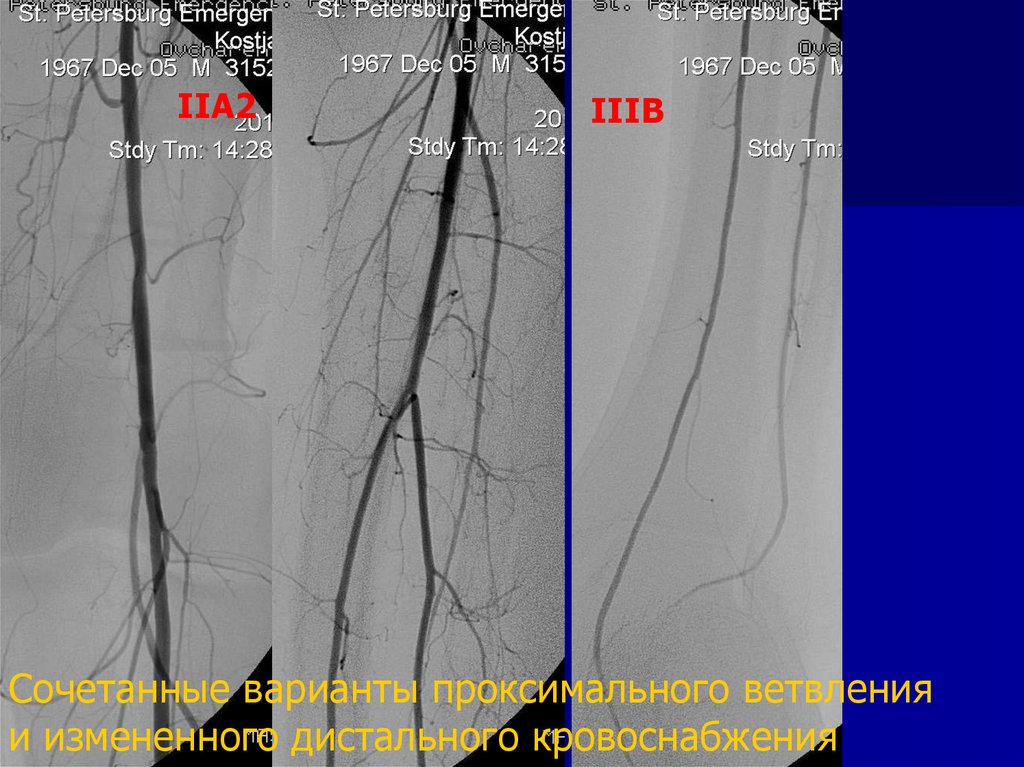

IIA2

IIIB

Сочетанные варианты проксимального ветвления

и измененного дистального кровоснабжения